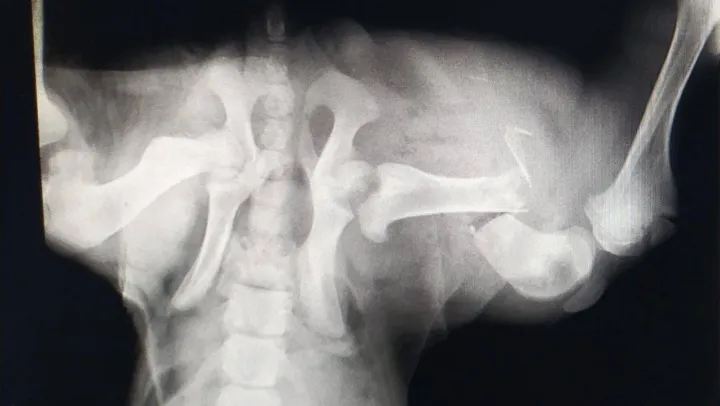

Edinilen bilgiye göre, İzmit'te trafik kazası geçiren sokak köpeği, bir vatandaş tarafından özel veteriner kliniğine götürüldü. Burada köpeğin genel durumunun çok kötü olduğu ve uyutulması gerektiği belirtildi. Ancak vatandaşın vicdanı el vermeyerek, sokak köpeğini Patilik Sokak Hayvanları Kasabasına getirdi. Patilik'te tetkiklerde köpeğin arka bacağında ciddi kırık bulunduğu belirlendi. Bursa Uludağ Üniversitesi Veteriner Fakültesi Cerrahi Anabilim Dalı Bölümünden Prof. Dr. Hakan Salcı'nın gözetiminde uzman hekimler tarafından kan tahlili yapılan ve röntgeni çekilen sokak köpeğinin ayağına plaka takıldı. Sokak köpeğine cerrahi operasyondan sonra ilaç tedavisi de uygulandı.

Patilik'ten yapılan açıklamada, 'Patilik Mutlu Sokak Hayvanları Kasabasına getirilen ve arka sağ bacağında kırık bulunan sokak köpeği başarılı bir operasyon geçirerek sağlına kavuştu. Patiliğ'e ilk getirildiğinde hayati verileri çok düşüktü, 6 aylık kangal sokak köpeği Patilik'te tekrar hayat buldu' denildi.